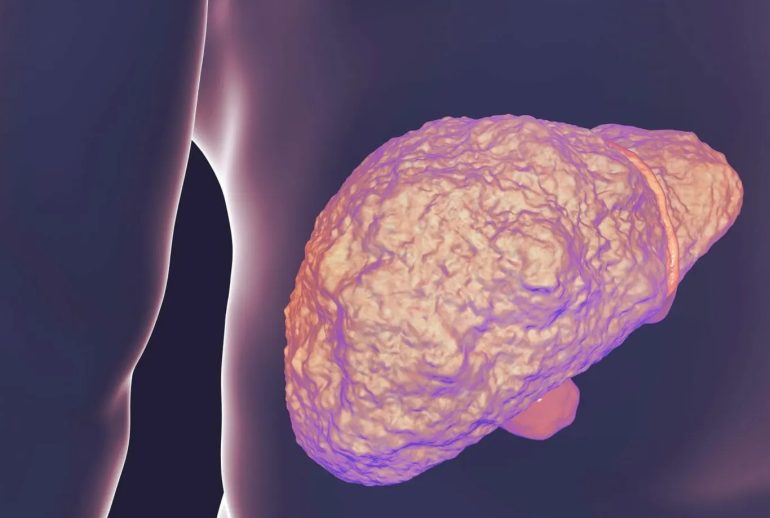

فیبروز کبدی به تشکیل بافت اسکار در کبد اشاره دارد. این وضعیت زمانی رخ میدهد که کبد در پاسخ به آسیب مزمن، شروع به تولید بافت فیبروزی میکند. با گذشت زمان، این بافت اسکار میتواند جایگزین بافت سالم کبد شود و عملکرد آن را مختل کند.